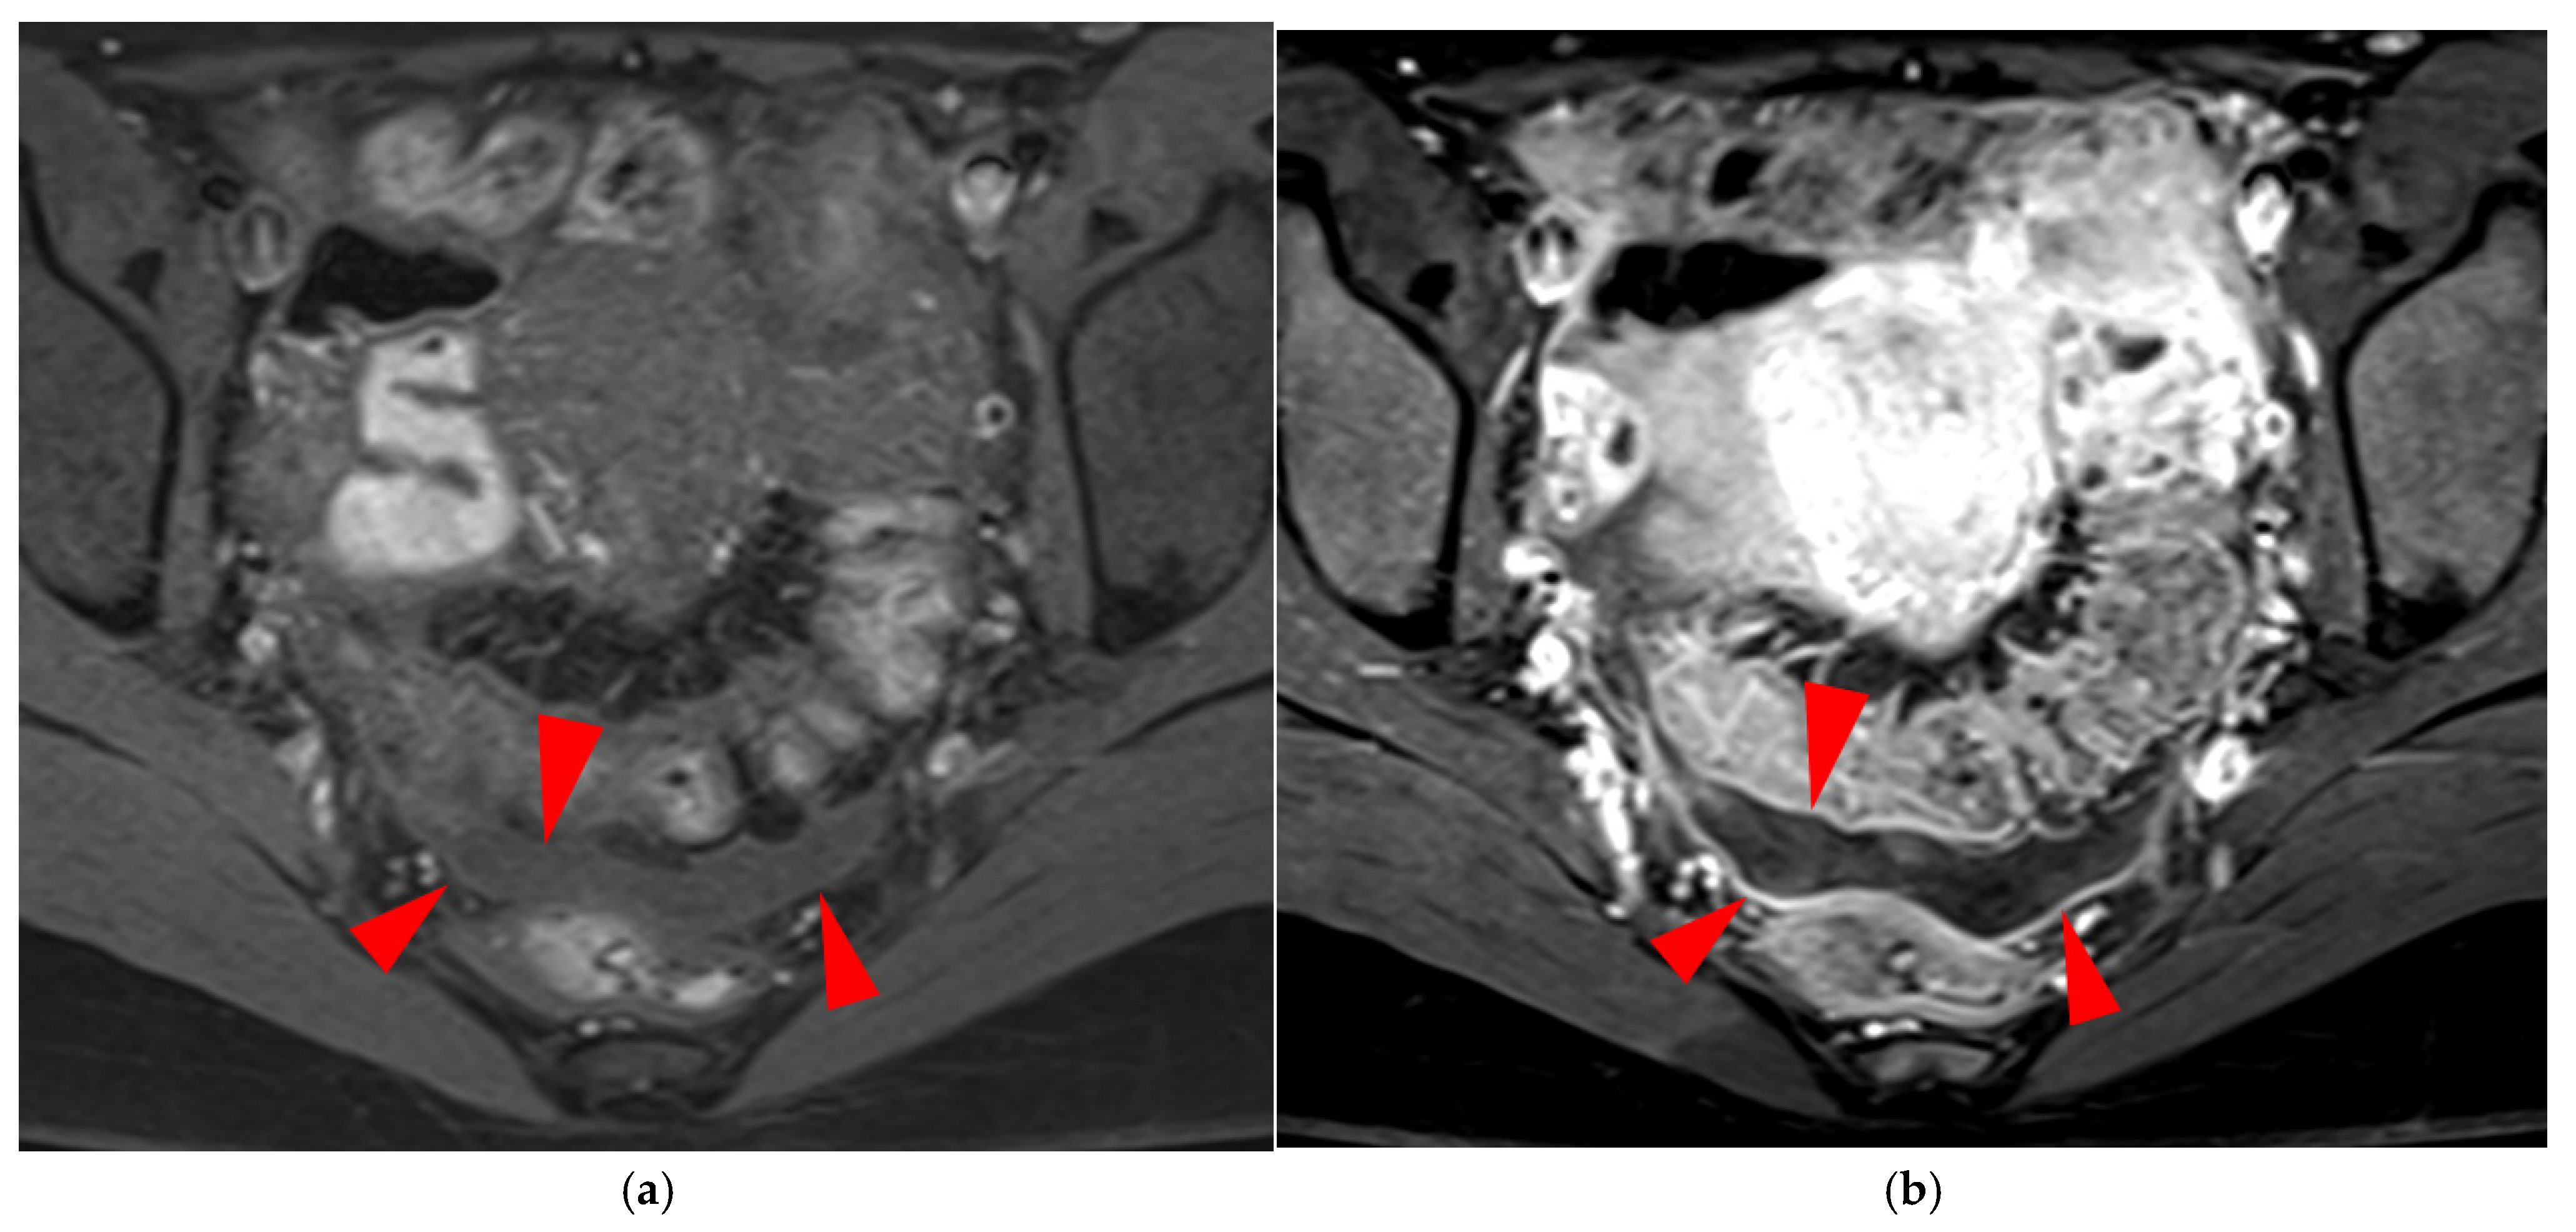

A type 6 USL is associated with adjacent pelvic “visceral” involvement in a broad sense. It most commonly affects the digestive tract (Figure 8 and Figure 9), with the rectum and rectosigmoid junction wall thickening: in this case, the lesion often appears as a “medallion-shaped” protrusion into the lumen. Less frequently, the urinary tract is affected (Figure 9 and Figure 10), involving the muscular layer of the bladder or even the distal ureter at the level of the common iliac artery, with stenosis potentially leading to upstream hydronephrosis. More rarely, as USLs are also close to nearby pelvic nerve structures (Figure 11), contiguous involvement of the inferior hypogastric plexus located in the sacro-recto-genital septum (a.k.a. Delbet sagittal fascia) beneath the distal two-thirds of the USL, or exceptional involvement of the sciatic nerve adjacent to the pelvic wall, is possible (Figure 12, Figure 13 and Figure 14).

2.3.1. “Kissing Ovaries”: A Form Straddling Between Type 5B and Type 6 USLs

Besides endometriomas, another type of ovarian involvement in DIE includes adhesions that cause the ovaries to retract medially across the midline, behind the uterus, into the pouch of Douglas. When the ovaries are displaced medially and are in close proximity, they are commonly referred to as “kissing ovaries”. Additionally, medialized ovaries on preoperative imaging expose the digestive tract to a 20% risk of involvement [22]. In our experience, the injection of a contrast agent is useful when there is doubt about an endometriotic rectosigmoid invasive lesion on T2WI, especially if a rectal filling was not performed. A markedly enhancing mucosa, which outlines rectosigmoid local wall thickening on post-contrast T1WI without fat suppression (forming a “medallion-shaped” lesion), is a valuable aid to diagnosis.

In the HTD MRI classification of USLs, the “kissing ovaries” sign is considered a form between types 5B and 6. In the case of concomitant rectal involvement, the USL is classified as type 6 (Figure 15); otherwise, it is classified as type 5B (comparable to a nodule with spiculated margins).

Figure 15. Pelvic MRI scan of a patient with a “kissing ovaries” sign and rectal involvement (i.e., HTD type 6 USLs). (a,b) Axial T2WI (a) and contrast-enhanced T1WI (b) show both ovaries in close proximity (“kissing ovaries” sign) (arrowheads) and rectosigmoid wall infiltration (arrows). (c) Sagittal contrast-enhanced T1WI shows rectosigmoid wall infiltration, appearing as a “medallion-shaped” lesion outlined by markedly enhancing mucosa (arrowhead).